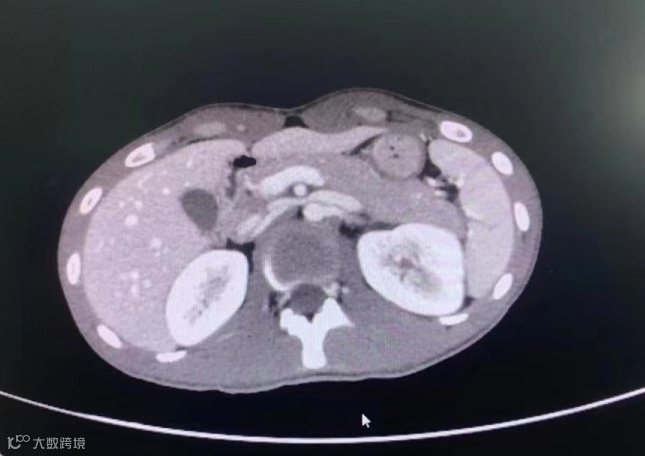

患者在当地医院做了B超、拍了片后,并未发现什么,但之后几天他一直不停排出血尿,于是为了进一步治疗来到市人民医院就诊。收入院后,经进一步CT检查,发现患者排血尿的原因是摔伤时导致“创伤性脾破裂和肾挫伤”。

肿瘤二区副主任、副主任医师张成文介绍,该患者因外伤导致脾破裂、肾挫伤,因此频繁尿血,必须尽快为其手术止血,根据患者病情选择合适的栓塞剂,一般不建议长效栓塞剂。

根据年轻患者的具体情况,需要考虑在手术止血的前提下尽量多保留患者的肾功能。

6月20日下午,张成文在刘建超医生的配合下,通过微创介入手术的方式,在患者的右大腿股骨沟动脉处进行穿刺,行肾动脉栓塞术,顺利为患者止血,成功保住了患者的肾脏。手术经历一个小时顺利完成,患者的血尿立即停止,无明显不适。